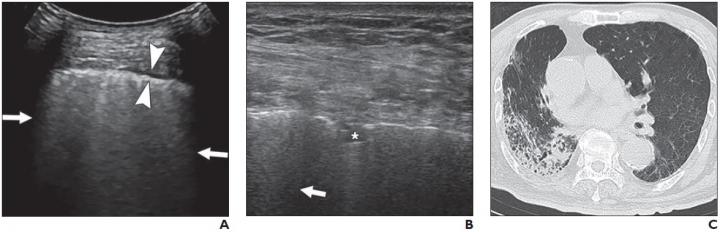

image: A and B, Lung ultrasound images obtained with convex (A) and linear (B) probes. Multiple confluent B-lines (arrows), patchy pulmonary consolidation (asterisk, B), and thickened pleural line (between arrowheads, A) are visualized. C, Chest CT image shows reticular and interlobular septal thickening and patchy, focal opacities associated with architectural distortion. This patient was classified in critical group and was assigned to severe group for statistical analysis.

All 28 patients (14 men and 14 women; age range, 21-92 years) had positive findings on both lung US and chest CT. On US, B-lines were present in 100% of patients, and 19 (67.9%) patients had pulmonary consolidation. Thickened pleural lines were observed in 17 patients (60.7%), and only one patient (3.6%) showed a small amount of pleural effusion.

"A thickened pleural line was more frequently observed on US in patients with longer time intervals after the initial onset of symptoms," Zhang et al. noted, adding that pulmonary consolidations--visualized as tissuelike hypoechoic regions, reflecting highly reduced air flow and increased quantity of inflammatory cellular exudate--were more common in severe and critical cases.